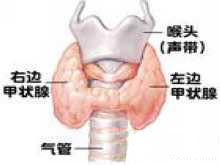

先天性甲状腺功能减低症

疾病介绍:先天性甲状腺功能减低症(简称甲低)又称克汀病或呆小病,多见于先天甲状腺缺陷,主要表现为体格和精神发育障碍,早期诊断和治疗可防止症状的发生或发展…【详细】